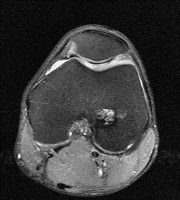

무릎 mri 간단히 봐주실 수 있으시나요 ㅠㅠ

안녕하세요 8년전 십자인대 수술하고 최근 무리한 운동에 무릎 불편감이 생겨서

mri 찍었습니다.

진단결과는 첫 찍은 병원에서 활액막염 이라는 진단을 받았습니다. 혹시 봐주실 수 있으실까요?

올라온 MRI가 단편적이라서 정확한 진단에 어려움이 있지만 십자인대에는 큰 이상이 있지는 않은것 같으며, 무릎관절내 물이 있는 것으로 보아 활액막염의 진단이 맞을 것 같습니다.

하지만 단편적인 영상이기 때문에 촬영병원에서 정확한 판독지 등을 받으시는 것이 좋겠습니다.